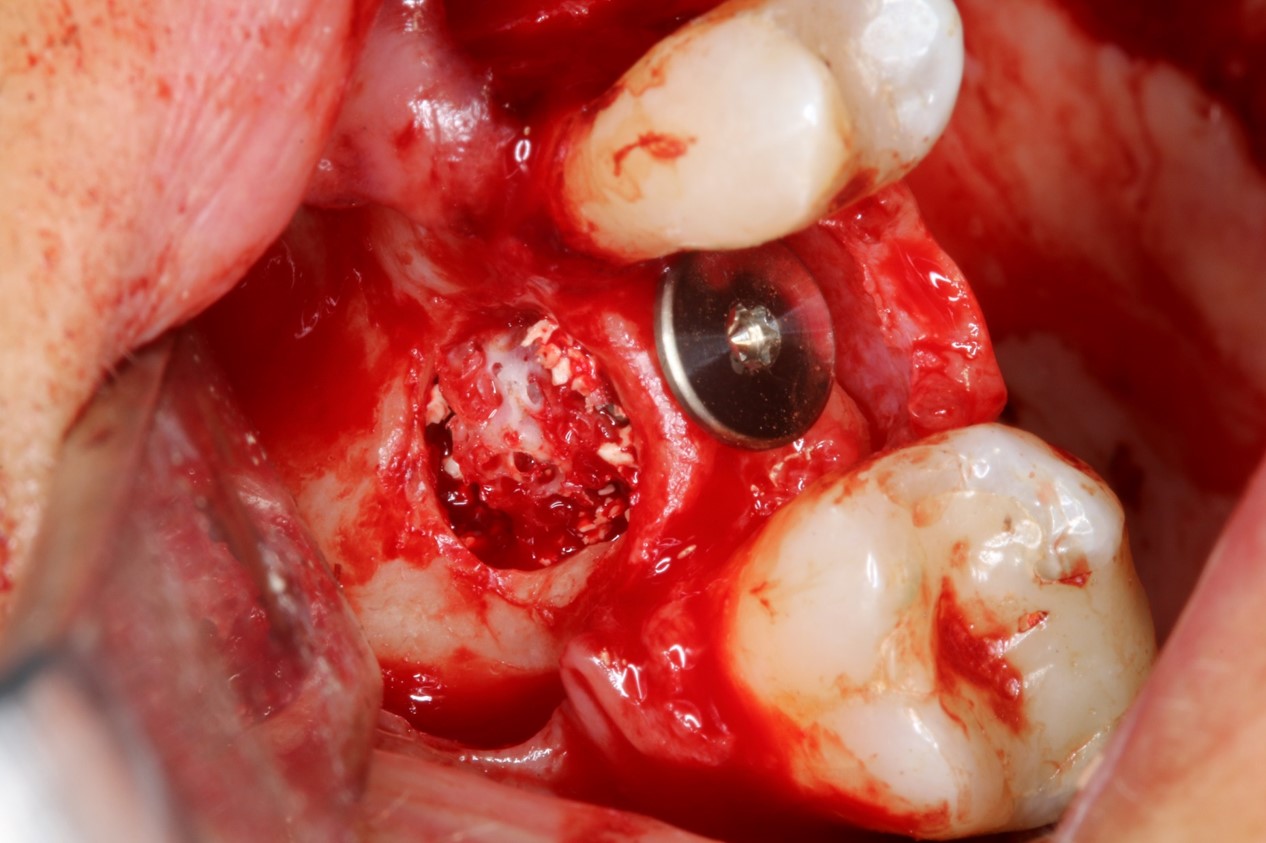

Clinical situation: 71-old patient with atrial fibrillation and Warfarin medication